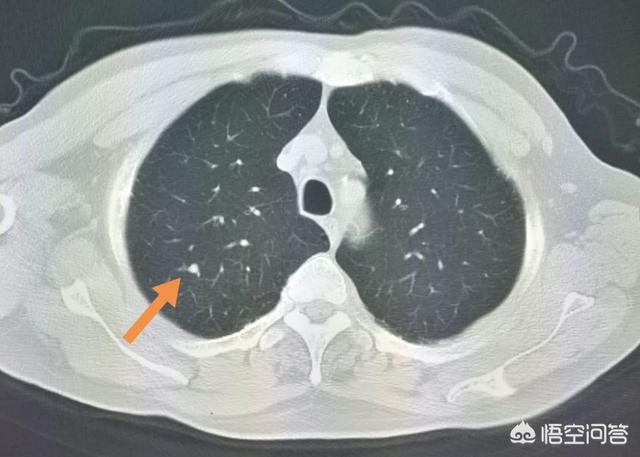

肺結節を見つけるための次のステップは、良性か悪性かを判断することである。良性の結節は、肺のリンパ節、形の悪い腫瘍、硬化性肺細胞腫など、間違いなく何でもないものである。残りの結節は良性または悪性の可能性があるもので、このような結節に対する治療の一般原則は経過観察を勧めることであり、結節の特異性(形態、大きさ、密度など)に応じて、見直しの時期は3ヵ月から1年である。結節の中には、炎症性結節のように経過観察中に吸収されて消失するものもあれば、肉芽腫のように変化しないものもあり、これは良い情報である。経過観察中に、結節の肥大、すりガラス結節の中の実成分や固形成分の増加、結節の緻密化、末梢血管が伸びているのが見えるなど、悪性の徴候があれば、積極的に対処すべきです。実際、人を見るように、正義の顔は、一般的に良い人、凶暴で悪質な悪人であり、いくつかの一時的な人の行動の観察を通じてのみ見ることができない、ルールは一般的に恐れていない場合は、悪い行動があることを発見した場合は、タイムリーに対処する必要があります。図1、左肺上部のすりガラス状の結節(オレンジ色の矢印)を発見し、2年以上経過観察したが変化なし。図2、右肺上部に2個の小さなすりガラス結節(オレンジ色の矢印)、2年後に消失した。図3、右肺上部のすりガラス状の小結節、3回目の経過観察で大きくなっているので、前向きに対処することを勧め、外科的病理検査でin situ癌、つまり前癌病変を発見すれば、肺癌の芽を摘むことができる。